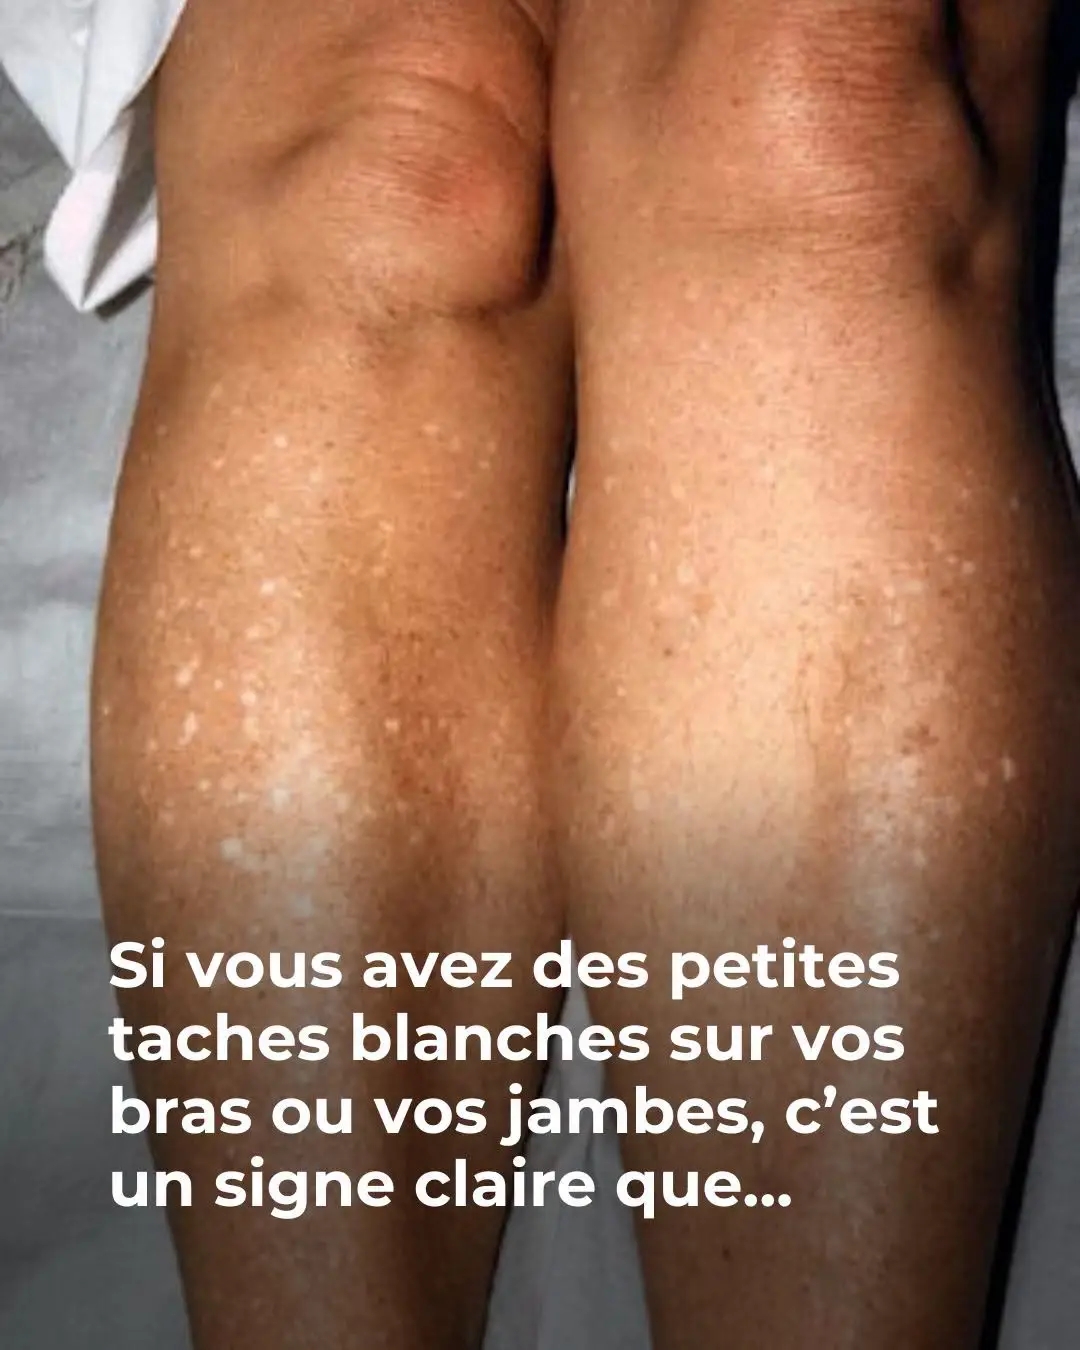

Si vous avez des petites taches blanches sur vos bras ou vos jambes, c’est un signe claire que…Voir plus

Votre bronzage n’est pas uniforme et quelques petites taches blanches, voire rouges, apparaissent sur certaines parties de votre peau ? Une dermatologue dévoile de quoi il s’agit et comment les traiter. Quoi de plus agréable que de se regarder dans le miroir et de constater l’apparition d’un joli tein hâlé, sur notre visage mais également … Lire plus